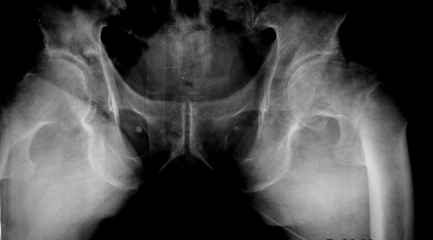

Чрезвертельный перелом у возрастного пациента

Уважаемые коллеги! Пациент с чрезвертельным переломом. Особенность случая в том, что ему 92 года, соматически сохранный.

Думаю, что больше транскутанной фиксации винтами он не выдержит. Вопрос - выдержит-ли такая фиксация при таком положении отломков.